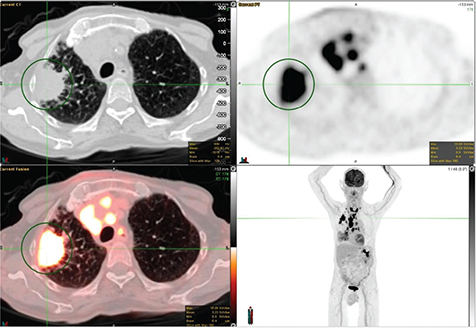

18F-FDG PET/CT demonstrates excellent performance in classifying SPNs as benign or malignant. Combining anatomical and metabolic imaging is synergistic by maintaining the sensitivity of CT and the specificity of PET, resulting in an overall significantly improved accuracy. 18F-FDG PET/CT can ultimately lead to considerable cost savings by reducing the number of biopsies and surgical interventions. Not all patients can undergo biopsy due to comorbidities or not being a surgical candidate or inaccessible to bronchoscopy. In such a scenario, radiation oncologists may prefer to treat lesions based on PET findings and clinical evaluation without biopsy confirmation. Furthermore, a pulmonary nodule in a patient with a known primary malignancy could represent a metastatic nodule of that primary malignancy, as shown in Figure 2.

Fig 2

Figure 2. Breast cancer with metastatic pulmonary nodules. FDG PET/CT images include axial CT (top left panel), axial PET (top right panel), fused axial PET/CT (bottom left panel), and PET image with maximum intensity projection (MIP) (bottom right panel). In the green circle, there is a small sub-centimeter left upper lobe pulmonary nodule with mildly increased FDG uptake (SUV max of 3.7) above the background of the mediastinal blood pool. There were additional sites of FDG-avid pulmonary nodules and breast nodules (not included on the PET/CT images though some can be seen on the MIP image) that were most suspicious of metastatic disease.